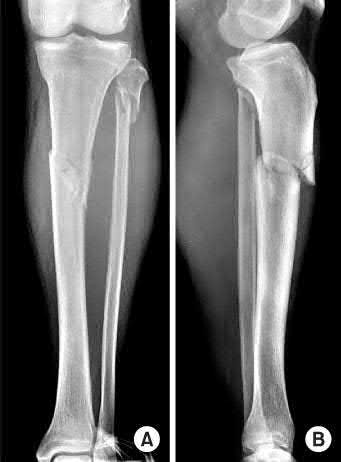

A 38-year-old male suffers the injury shown in Figure A. During operative fixation, free osteoarticular fragments are encountered and reconstruction of these pieces is attempted. Postoperatively, which of the following will have the most beneficial effect on the healing potential of the surviving chondrocytes within these reconstructed articular segments?

Figure A demonstrates a comminuted tibial plateau fracture with significant intra-articular involvement. Basic science evidence has demonstrated that post-operative gentle compressive loading may have a positive impact on articular cartilage healing; however, excessive shear loading may be detrimental.

Irrgang et al provide guidelines for rehabilitation following surgical management of articular cartilage lesions of the knee. They state that after articular cartilage repair, exercises to enhance muscle function must be done in a manner which minimizes shear loading of the joint surfaces in the area of the lesion. The authors also discuss the benefits of gentle compressive loading and motion of the joint, and its positive effects on chondrocyte nutrition.

Furthermore, they recommend a period of protected weight bearing as often being necessary, and that this should be followed by progressive loading of the joint.